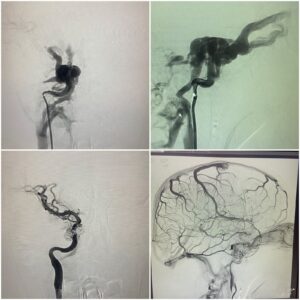

ऋषिकेश। एम्स की कार्यकारी निदेशक एवं सीईओ प्रोफेसर (डॉ.) मीनू सिंह के निर्देशन में संस्थान के इंटरवेंशन रेडियोलॉजी विभाग में उच्च तकनीकी वाले न्यूरो इंटरवेंशन जैसे कैरोटिड स्टेंटिंग (खून की नस में सिकुड़न ) ए.वी.एम व ए.वी.एफ( खून की नसों का गुच्छा) , स्ट्रोक (लकवा) एन्यूरिजम (खून की नसों का गुब्बारा व नसों का फटना) समेत कई अन्य तरह की बीमारियों का बिना किसी चीरफाड़ के इलाज उपलब्ध है। बताया गया है कि यह उपचार एम्स अस्पताल में मरीजों को बीते आठ महीने से आयुष्मान भारत योजना के तहत निशुल्क दिया जा रहा है।

संस्थान में यह कार्य दिल्ली एम्स से प्रशिक्षित एवं वर्तमान में एम्स ऋषिकेश के इंटरवेंशन रेडियोलॉजी विभाग (भूतल बी- ब्लॉक) में कार्यरत सहायक आचार्य डॉ. बी.डी. चारण (डी.एम. न्यूरोइंटरवेंशन) द्वारा मरीजों में इस तरह की बीमारियों के उपचार को अंजाम दिया जा रहा है।

डॉ. चारण के मुताबिक इस विधि के तहत जांघ की खून की नस में 2 एमएम का पाइप डालकर ब्रेन तक पहुंच बनाई जाती है, उसके बाद बीमारी का बिना चीरफाड़ किए इलाज किया जाता है। उन्होंने बताया कि चूंकि इस उपचार में चीरफाड़ नहीं किया जाता है, लिहाजा मरीज को अस्पताल अथवा आईसीयू में निहायत कम समय तक ही रुकना पड़ता है और मरीज की जल्दी छुट्टी कर दी जाती है।